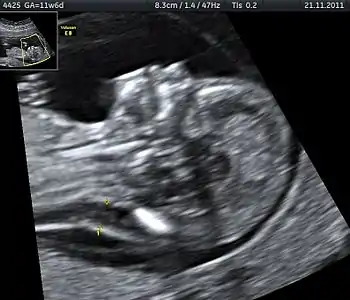

Enlarged NT and absent nasal bone in a fetus at 11 weeks with Down syndrome

Overall, the most common chromosomal disorder is Down syndrome (trisomy 21). The likelihood rises with maternal age from 1 in 1400 pregnancies below age 25, to 1 in 350 at age 35, to 1 in 200 at age 40.[4]

In another study values of 79.6% and 2.7% for the combined screening were then improved with the addition of second trimester ultrasound scanning to 89.7% and 4.2% respectively.[12] A further study reported detection of 88% for trisomy 21 (Down syndrome) and 75% for trisomy 18 (Edwards syndrome), with a 3.3% false-positive rate.[13] Finally, using the additional ultrasound feature of an absent nasal bone can further increase detection rates for Down syndrome to more than 95%.[14]